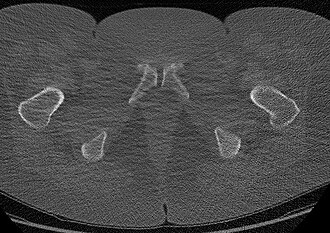

Normal lumbar spine phantom with healthy vertebral bodies, intact discs, spinal canal, and nerve roots

L4-L5 posterolateral disc herniation compressing the L5 nerve root with disc desiccation, annular tear, and...

Thoracolumbar compression fracture (T12) with vertebral body height loss, retropulsed fragment, marrow edema, and...

Lumbar spinal stenosis with ligamentum flavum hypertrophy, facet joint arthropathy, disc bulge, and narrowed central canal